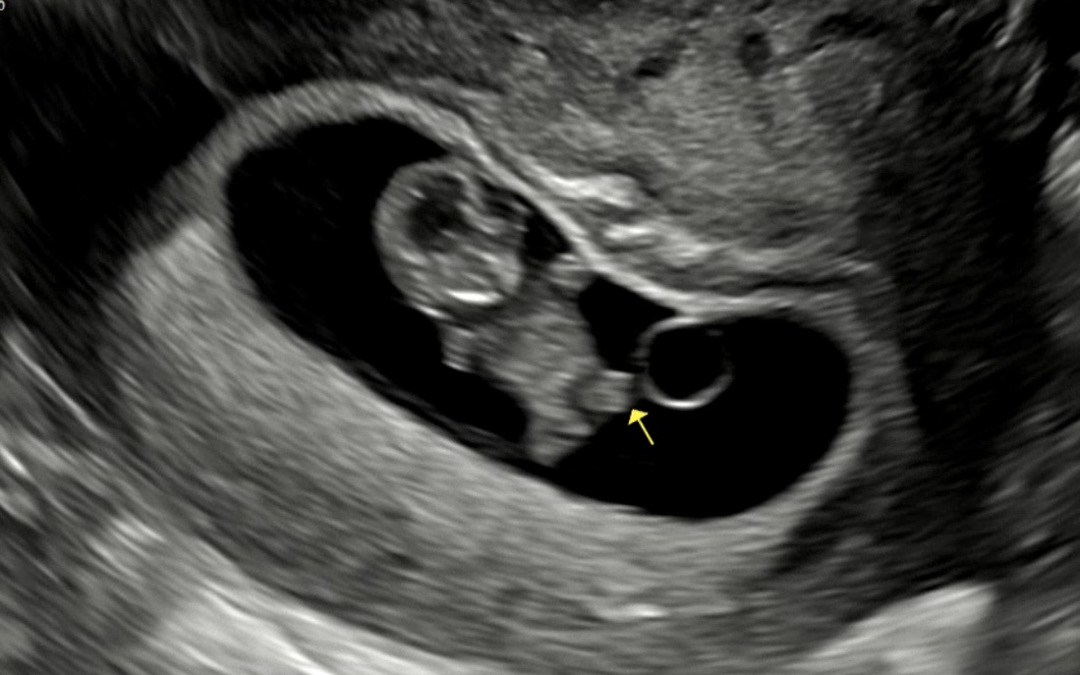

9주차 젤리곰 보고왔어용🧸

9주 1일차 검진 다녀왔어요! 곰돌이 키링 같이 넘 귀여워서 올려보아요ㅎㅎ 둠칫둠칫 살짝씩 움직이더라구요ㅠㅠ 넘 기특하고 귀여웠어요💗💕